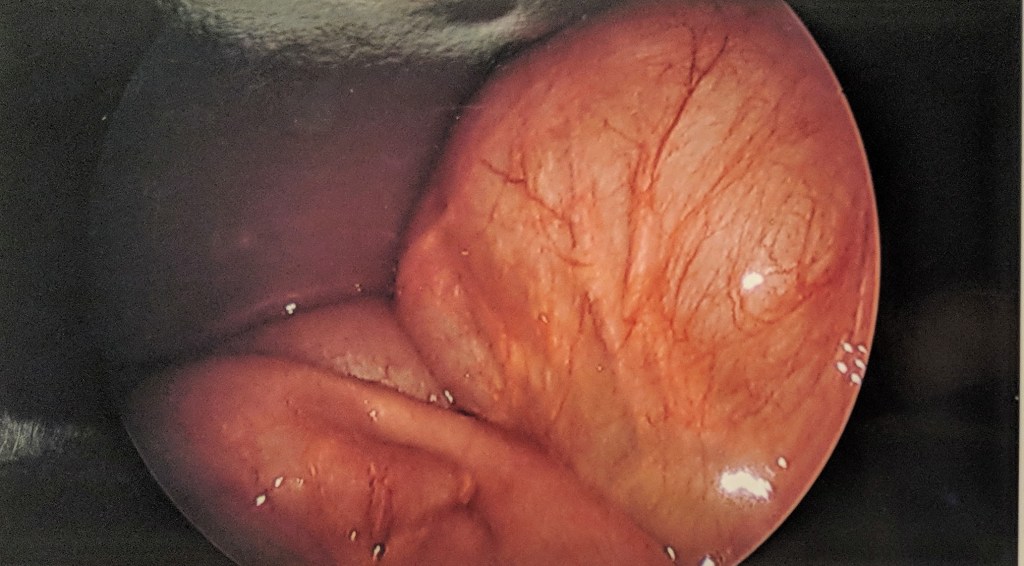

The omentum is a fascinating apron of fat within the abdomen which not only keeps our organs in place but also plays an immunological role. The omentum’s central role is the abdominal defenseman, it adheres to sites of inflammation and provides leukocytes to combat infection. In Theo’s case the omentum had adhered to the sites of his previous bowel surgeries, stretching across a portion of his small intestine. This part of the small bowel proceded to push through the stretched omentum- creating a donut-like shape- and then curved back around and came back through the same hole.

This kink in the intestine had been developing since Theo’s first symptoms in February. During the procedure, the team trimmed back the omentum, releasing Theo’s small intestine. They then inspected most of small intestine to examine other sites of adhesion but felt no further alterations were necessary. We found this pathophysiology to be fascinating, as did Theo. He even got surgical pictures as a keepsake. He enjoys retelling the story to his sisters with these graphic images.